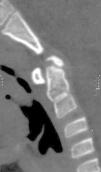

Se describe el caso de un varón de 7 años que es trasladado a Urgencias de Pediatría (UPED) con bajo nivel de consciencia tras traumatismo craneoencefálico secundario a caída en bicicleta. La familia refiere traumatismo frontal contra un bordillo, sufriendo una pérdida de consciencia inicial de unos 10 s de duración. A su llega a UPED, se constata tendencia al sueño, con Glasgow 14/15. Se realiza inmovilización cervical con collarín rígido y TC cráneo-cervical en la que se observa la persistencia de parte de la sincondrosis de la odontoides y un pequeño fragmento óseo en el extremo distal de la misma, no fusionado al resto, de 7mm de diámetro (figs. 1–3). Este se corresponde con un osículo de Bergmann (ossiculum terminale de Bergmann) y no debe confundirse con el os odontoideum (falta de fusión entre la apófisis odontoides y el cuerpo del axis) ni con una fractura de odontoides1. Dicho osículo es un hallazgo normal durante el proceso de osificación de la odontoides, tratándose de un centro de osificación secundario, que aparece en torno a los 3-6 años, fusionándose en torno a los 12 años de edad. No precisa tratamiento alguno, ya que es estable y raramente da síntomas2. Nuestro paciente evolucionó favorablemente, siendo alta tras 24 h de observación, recomendándose seguimiento posterior en la consulta de Traumatología.